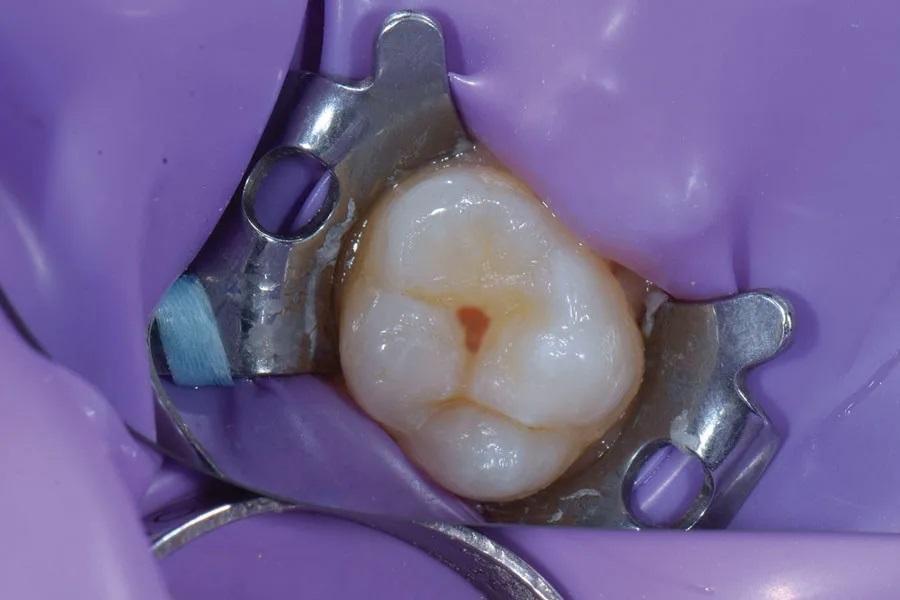

Пациент, мужчина 32 лет, направлен в клинику автора с жалобами на чувствительность зуба в левом верхнечелюстном квадранте к холоду и сладкому. При зондировании выявлен окклюзионный кариес класса 1 в центральной ямке окклюзионных фиссур зуба 2.6 (Фото 1). Выполнены прицельные рентгенограммы для оценки распространенности поражения и исключения вовлечения пульпы. Пациенту разъяснено наличие заболевания; показано прямое восстановление композитной смолой для устранения боли и чувствительности и восстановления функции и эстетики зуба. Пациент согласился; лечение запланировано на следующую неделю.

Фото 1. Пациент жаловался на чувствительность и боль в боковом моляре при воздействии сладких или холодных раздражителей. В зубе 2.6 был обнаружен кариес 1-го класса с окклюзионной стороны.